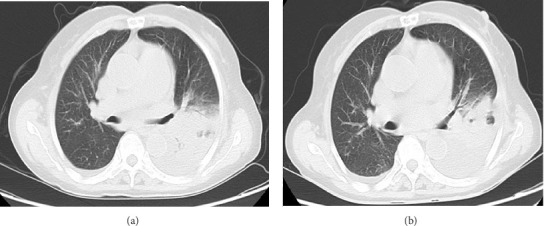

Psittacosis is a zoonotic disease caused by Chlamydia psittaci and is commonly found in birds and poultry. Human infection is uncommon, and most cases are sporadic. Infection of extrapulmonary organs by Chlamydia psittaci is extremely rare. A rare case of infective endocarditis complicated by pneumonia caused by Chlamydia psittaci was reported, which was diagnosed using metagenomic next-generation sequencing (mNGS). The patient recovered after receiving appropriate anti-infective treatment. Discussion on the pathogenesis, diagnosis, and treatment of this disease based on recent literature reports aimed to improve the prognosis of similar patients and enhance the understanding of clinicians.